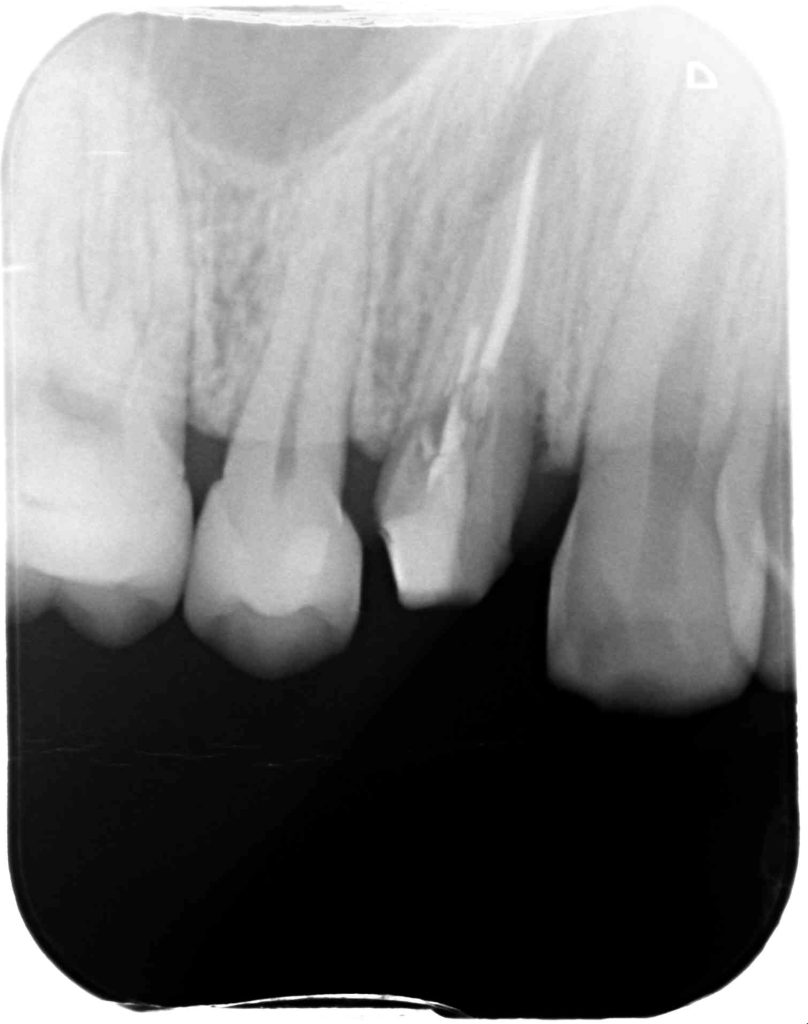

下記の症例は7年前の来院時に外部吸収を起こしていた為、患者さんに抜歯を勧めていました。

その時は、さほど自覚症状もなく、経過観察となりましたが、今回は被せ物が取れ、口臭がするという事で久しぶりに当医院に来院していただきました。

神経がないので痛みというより違和感程度でしたが、抜歯に同意していただき、抜歯と同時にインプラント治療を行い、できるだけ負担を減らし治療期間を短縮する計画を立てました。